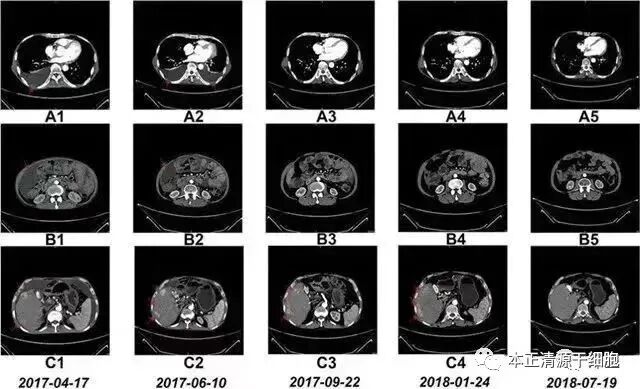

△ NK细胞干预前和干预期间的CT扫描结果

案例2:国内一名60岁的卵巢癌晚期患者,在接受了体外扩增,高度活化的同种异体NK细胞的干预后,CA125水平从11,270降至580,所有腹水都消失了。此外,CT扫描的肿块体积减小,并且没有出现副作用。

案例3:一名广泛期小细胞肺癌患者,在进行4个疗程化疗和4次高度活化NK细胞回输后,患者第一次进行干预后的CT复查,结果显示,肿瘤缩小到了原来的1/8。而且距发病第六年的CT复查中,仍旧没有发现任何异常及复发的迹象。